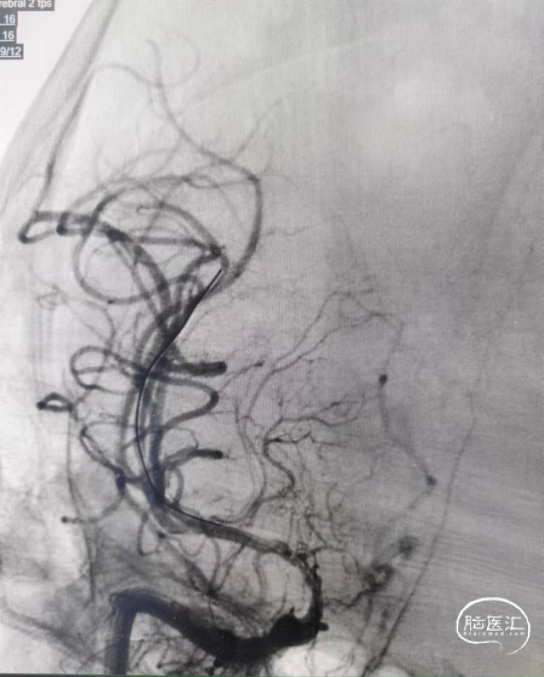

术后影像:全脑不同体位造影。